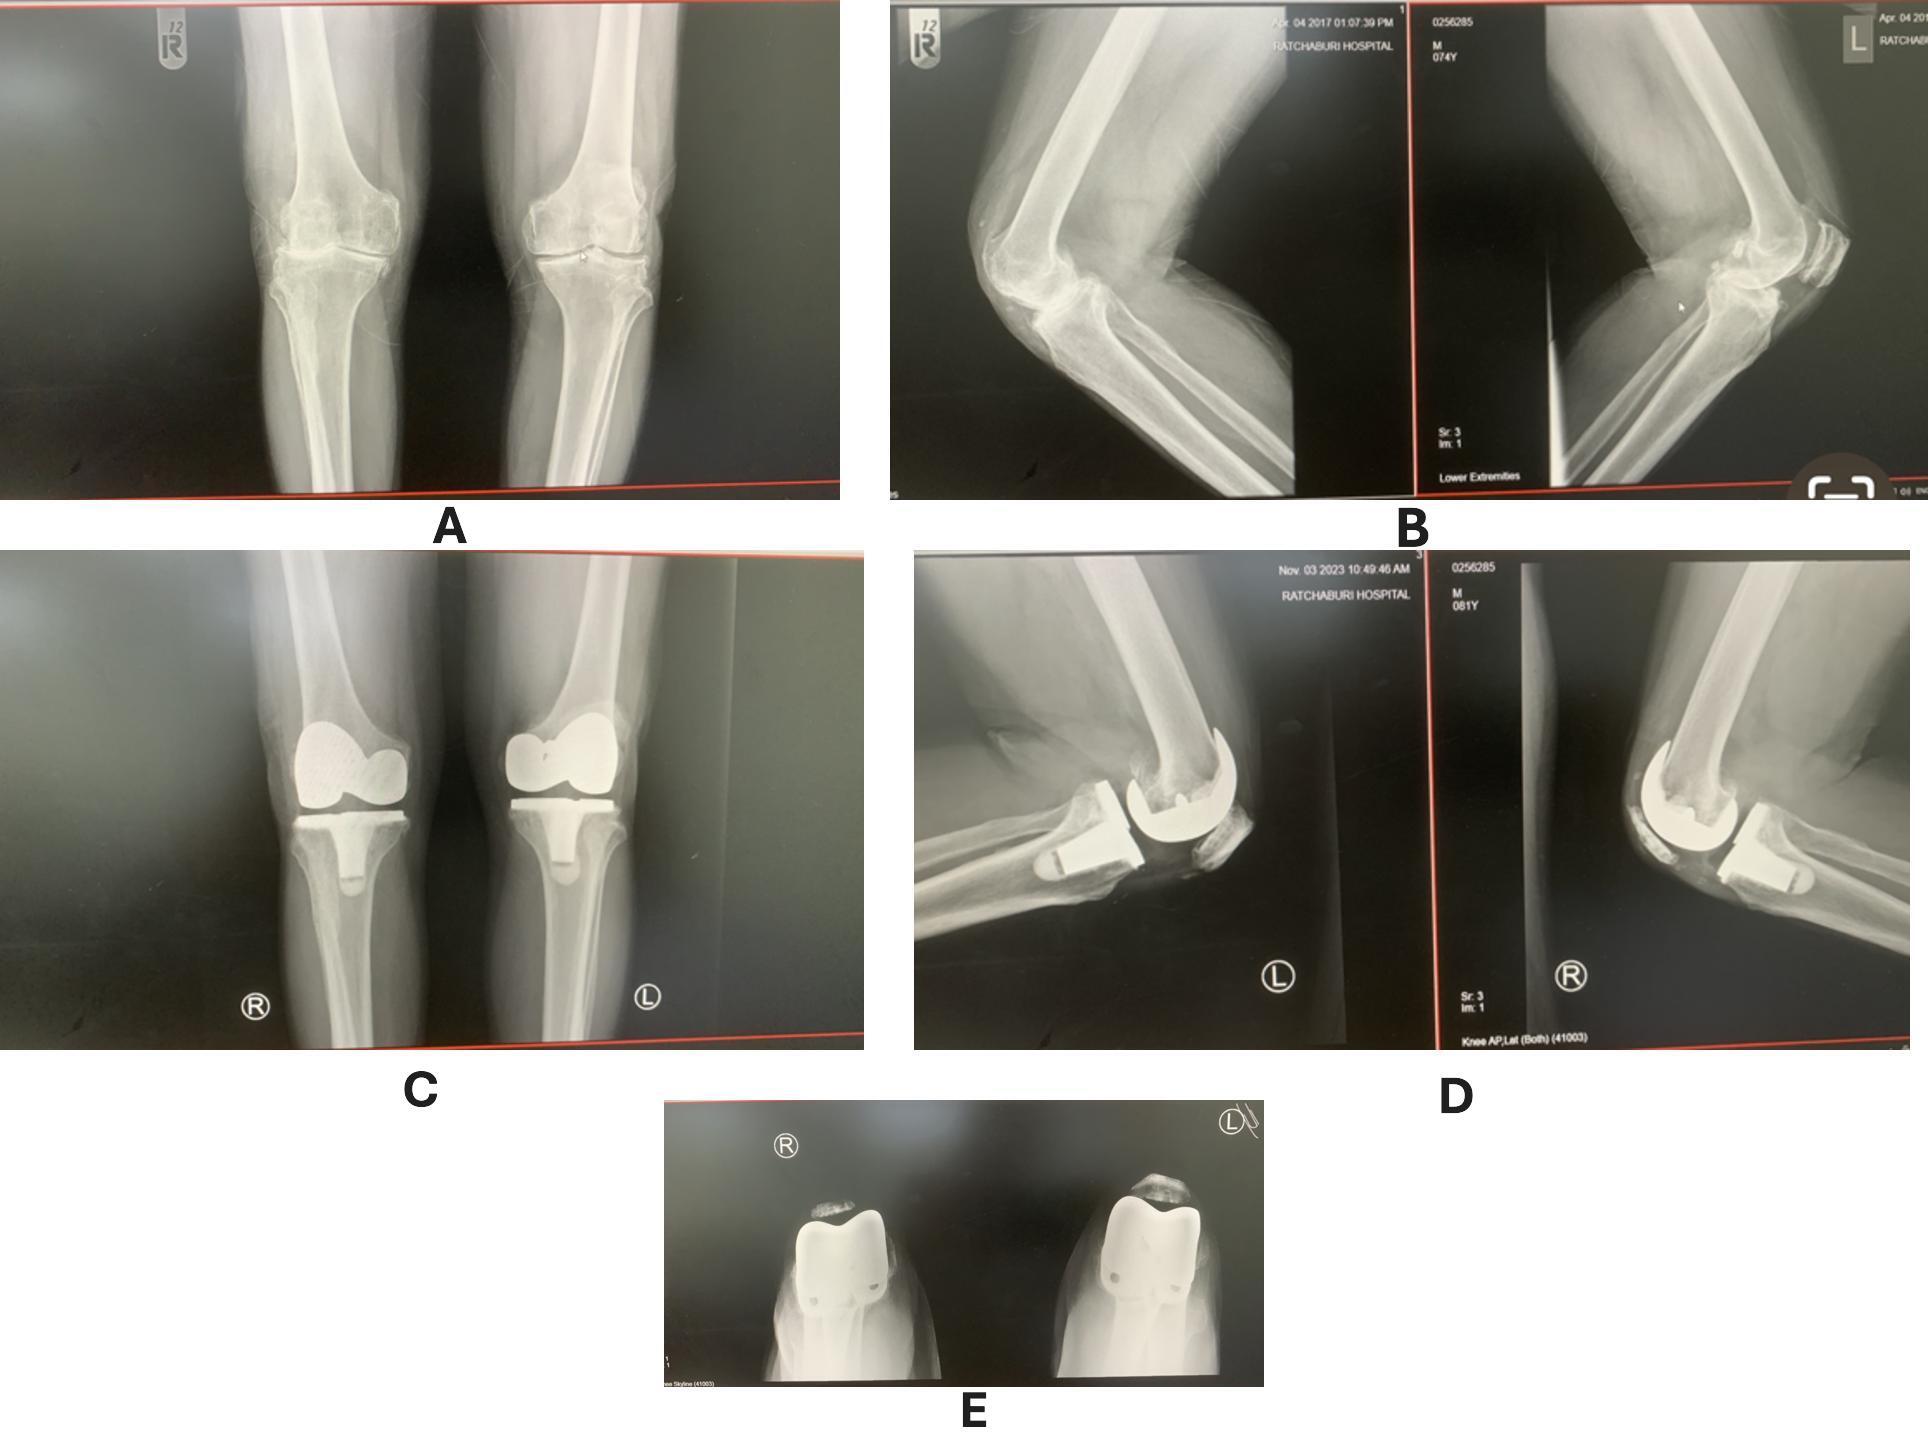

A 74-year-old man with a history of open knee injury and subsequent complete patellectomy 40 years ago presented to Ratchaburi Hospital in 2017 with bilateral knee pain. He used crutches for 40 years and was unemployed. The patient was generally healthy but had high blood pressure treated with amlodipine 5 mg and frequently used NSAIDs for knee pain. Their overall health was classified as ASA II, and they had no major heart risk factors (RCRI score of 0). He underwent left TKA in December 2017 and plans to get the right TKA in 2019. The COVID-19 pandemic delayed a schedule until February 2022, when it was finished.

Preoperative examination of the right knee revealed a range of motion of 0-120 degrees with passive extension, 10 degrees of extensor lag, and intact medial and lateral collateral ligaments.

There was no neurovascular compromise. The patient received combined spinal anesthesia and a femoral nerve block during surgery. Following physical and radiographic assessment, the patient underwent TKA with a cemented, fixed-bearing posterior-stabilized prosthesis (NexGen LPS Fixed Bearing Knee, Zimmer Biomet, Warsaw, Indiana, USA). An 8-mm autologous bone graft harvested from the medial distal femoral condyle was utilized for patellar reconstruction. This neo-patella was resurfaced with a cemented patellar prosthesis and sutured to the extensor mechanism. The patient was closely monitored. Two years after surgery, his knee fully functions without pain and could bend from 0 to 120 degrees, the same as his contralateral knee. The radiograph showed no signs of graft migration or resorption.

A rehabilitation program, including quadriceps exercises and active knee range of motion, was initiated at 8 and 12 weeks postoperatively. Postoperative radiographs demonstrated a well-aligned prosthesis. At eight weeks, the patient started full weight-bearing ambulation. By twelve weeks, the patient achieved a range of motion of 0-120 degrees with excellent patellar tracking and no effusion. Two years later, the neo-patella was still in place and showed no resorption or migration on radiography. (Figure 2) The Oxford Knee Society Score was 45, and the Feller Patella Score was 26. The postoperative alignment and range of motion for his knees are shown in Figure 3.